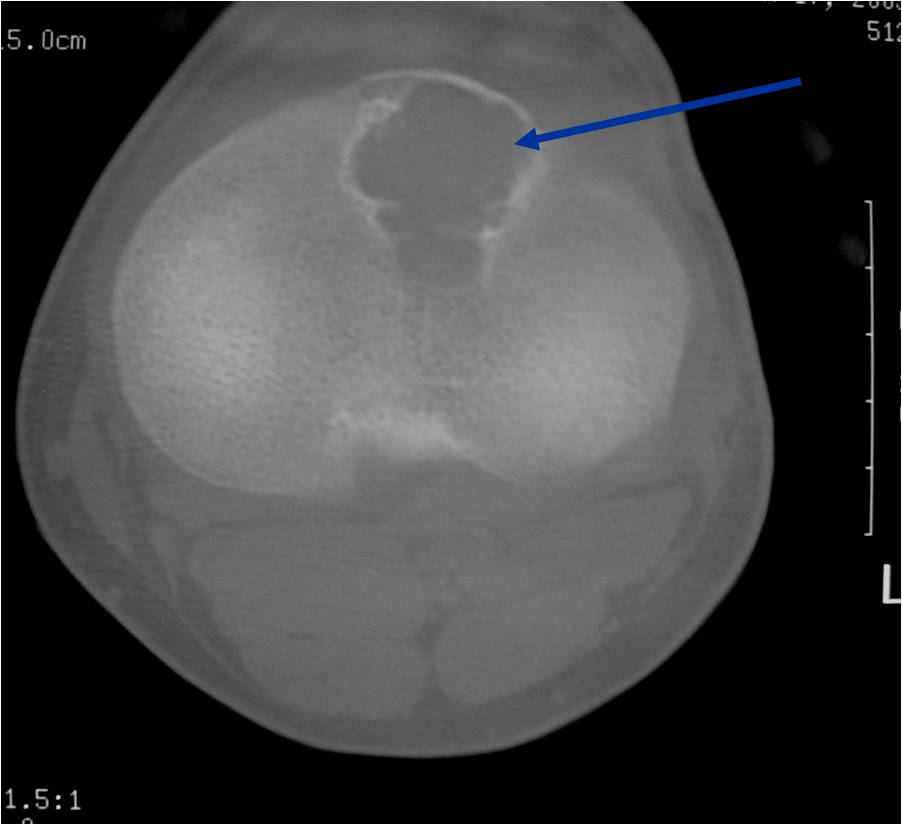

General Information Enchondroma is a benign indolent intramedullary hyaline cartilage neoplasm Accounts for 10% of all benign osseous tumors Limited growth, most lesions are less than 5 cm in maximal dimension Bones grow from a cartilaginous growth plate that...